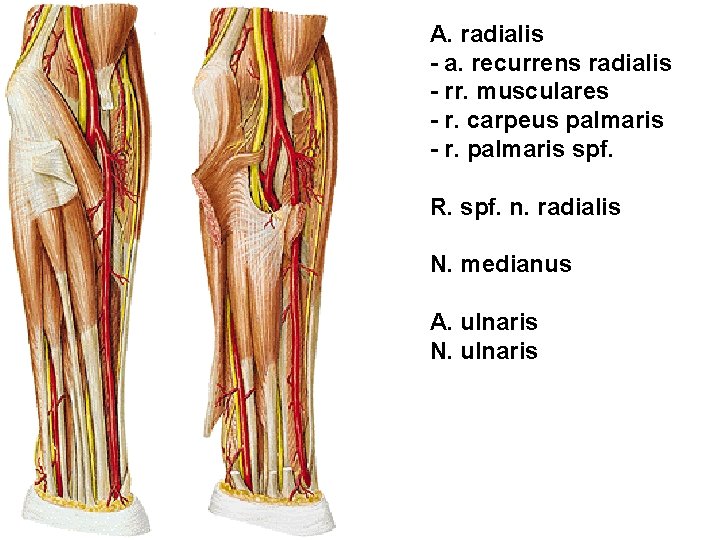

A. radialis - a. recurrens radialis - rr. musculares - r. carpeus palmaris - r. palmaris spf. R. spf. n. radialis N. medianus A. ulnaris N. ulnaris